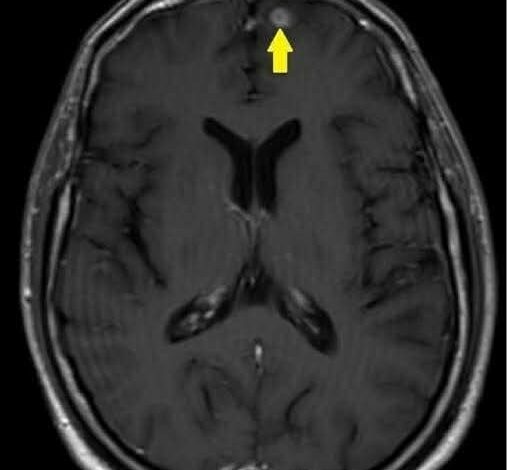

طلبت فحص قاع العين، الذي كشف عن ارتفاع ضغط السائل الدماغي، وتبعته أشعة أظهرت ورمًا صغيرًا في المخ.

الورم كان يؤثر على كهرباء دماغه، ويشوه ردود أفعاله وسلوكه… وحياته كلها.